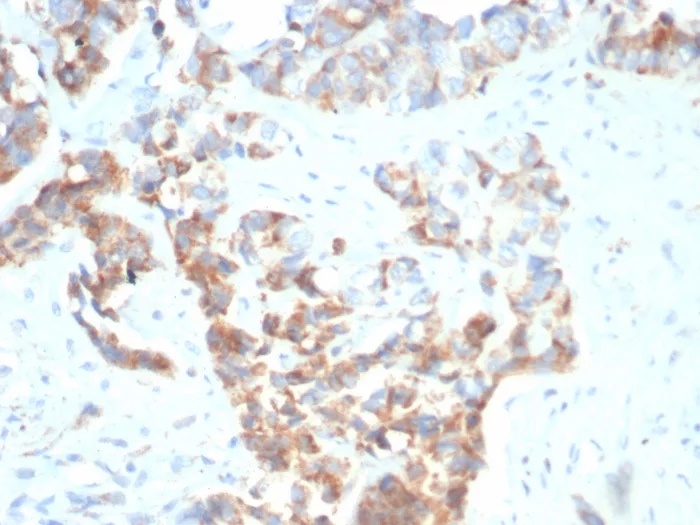

Formalin-fixed, paraffin-embedded human gastric carcinoma stained with CD269 / TNFRSF17 Mouse Monoclonal Antibody (BCMA/7253). Inset: PBS instead of primary antibody; secondary only negative control.